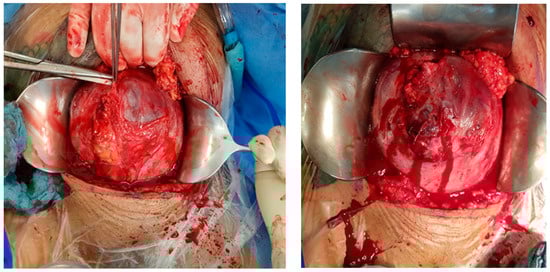

Sonographic findings (Figure 11):

Figure 11.

Increased placental blood flow on 2D ultrasound. Red color represents increased placental blood flow moving to the transducer; blue color represents placental blood flow moving leaving away from the transducer.

Histological findings:

- Hysterectomy specimen, 676.0 g, with parts of a placenta growing into the myometrium. Placenta growing into the myometrium, also extending directly to the ventral periuterine connective tissue.

- So-called placenta increta and also percreta with reduced decidua in the region of the decidua in the region of the fimbrial suture.

- Tubal and fimbrial funnels with edematous stroma. Inconspicuous fallopian tube.